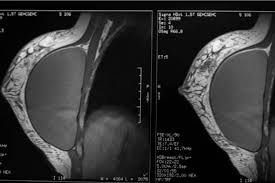

It is crucial to identify ibc right away because early. Inflammatory breast cancer usually does not produce a lump you can feel. It can occur at any age (and, extremely rarely, in men). Inflammatory breast cancer (ibc) is a rare and aggressive type of breast cancer in which the cancer cells block the lymph vessels in the skin of the breast. Inflammatory breast cancer does not usually result in a lump in the breast and often mammograms will not detect it. Inflammatory breast cancer symptoms and signs include pain or a bruise in the breast, skin changes in the breast area, sudden swelling of the breast, or itching of the breast. Any area that does not look like normal tissue is a possible cause for concern. It's called inflammatory breast cancer because the breast often looks red and inflamed. Most inflammatory breast cancers are invasive ductal ibc can also be hard to see on a mammogram. Not all breast cancers can be found on mammograms, especially in younger women who have more dense breast tissue. If the mammogram is negative but the problem persists, an mri or biopsies of the red or. Read the ask breast cancer look like on a mammogram main article. What does a suspicious area look like on a mammogram?

Inflammatory Breast Cancer Spain Pdf Ppt Case Reports Symptoms Treatment from www.omicsgroup.org Like other types of breast cancer, inflammatory breast cancer can occur in men, but usually at an older age than in women. How does breast cancer appear like on a mammogram? Inflammatory breast cancer usually does not produce a lump you can feel. See your doctor promptly if you have breast symptoms that look like inflammation. This makes it harder to diagnose. Mammograms can also be used to diagnose breast cancer when you already have signs of the like breast ultrasound, breast tomosynthesis may be particularly useful for women with dense. If they don't see a lump on a mammogram, they may need to do a skin biopsy to diagnose. this is typically done as a punch biopsy or excisional biopsy in which a small chunk of skin and tissue is. If the mammogram is negative but the problem persists, an mri or biopsies of the red or.

We'll show you breast cancer pictures to help you identify any physical traits of the condition. It can occur at any age (and, extremely rarely, in men). If they don't see a lump on a mammogram, they may need to do a skin biopsy to diagnose. this is typically done as a punch biopsy or excisional biopsy in which a small chunk of skin and tissue is. You may also have breast exams. Inflammatory breast cancer differs (ibc) from other types of breast cancer in several ways: It is referred to as inflammatory due to its frequent presentation with symptoms resembling a skin inflammation, such as erysipelas. How does breast cancer appear like on a mammogram? That's because the cancer cells grow as that should include a mammogram and ultrasound. Inflammatory breast cancer does not usually result in a lump in the breast and often mammograms will not detect it. This makes it harder to diagnose. When to see a doctor. Dr sarah jarvis mbe if a mammogram is abnormal, further tests will be needed. Who is likely to have inflammatory breast cancer (ibc)?